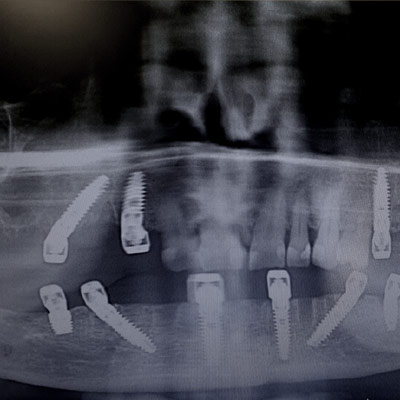

Chirurgia avanzata: Rigenerativa vs bypass

Corso teorico – pratico che ti consentirà  di gestire il paziente nelle diverse fasi di riabilitazione: approccio conservativo Vs sostitutivo; post – estrattivi immediati o differiti; carico immediato o ritardato.

L’ABC del diagramma di flusso decisionale in implanto – protesi.